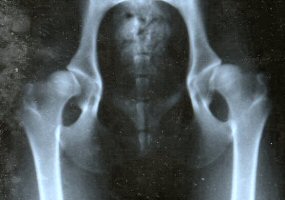

Good Hip Score Poor Hip Score

X Ray showing joints yielding a poor hip score. The balls (femoral heads) fit loosely into wide, open sockets (acetabulae).

Hip dysplasia is a partial dislocation of the ball joint resulting in lameness when dogs are severely affected. It is largely inherited, so can only be reduced by testing and careful selection of breeding stock. Both boxer parents should have test scores less than 14.89, which is the average for the breed in New Zealand. However, positive results from the parents do not guarantee low scores for all their puppies, but the risk of problems is much less than if the parents are not tested. As part of a long term breeding plan, as many dogs as possible in a line should be tested to establish a significant average score. Dogs must be over 12 months old before they can be tested.